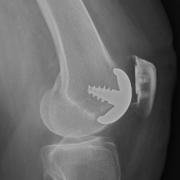

X-ray from the side, showing how the implant is anchored.